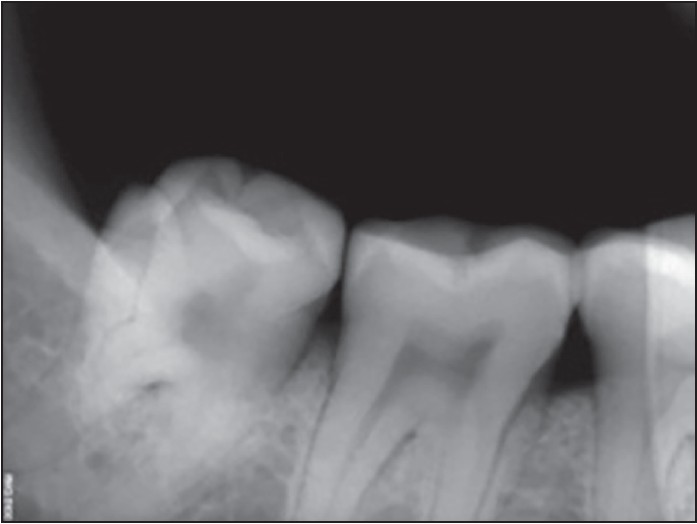

Figure 5: Protostylid on 38 with a rudimentary root